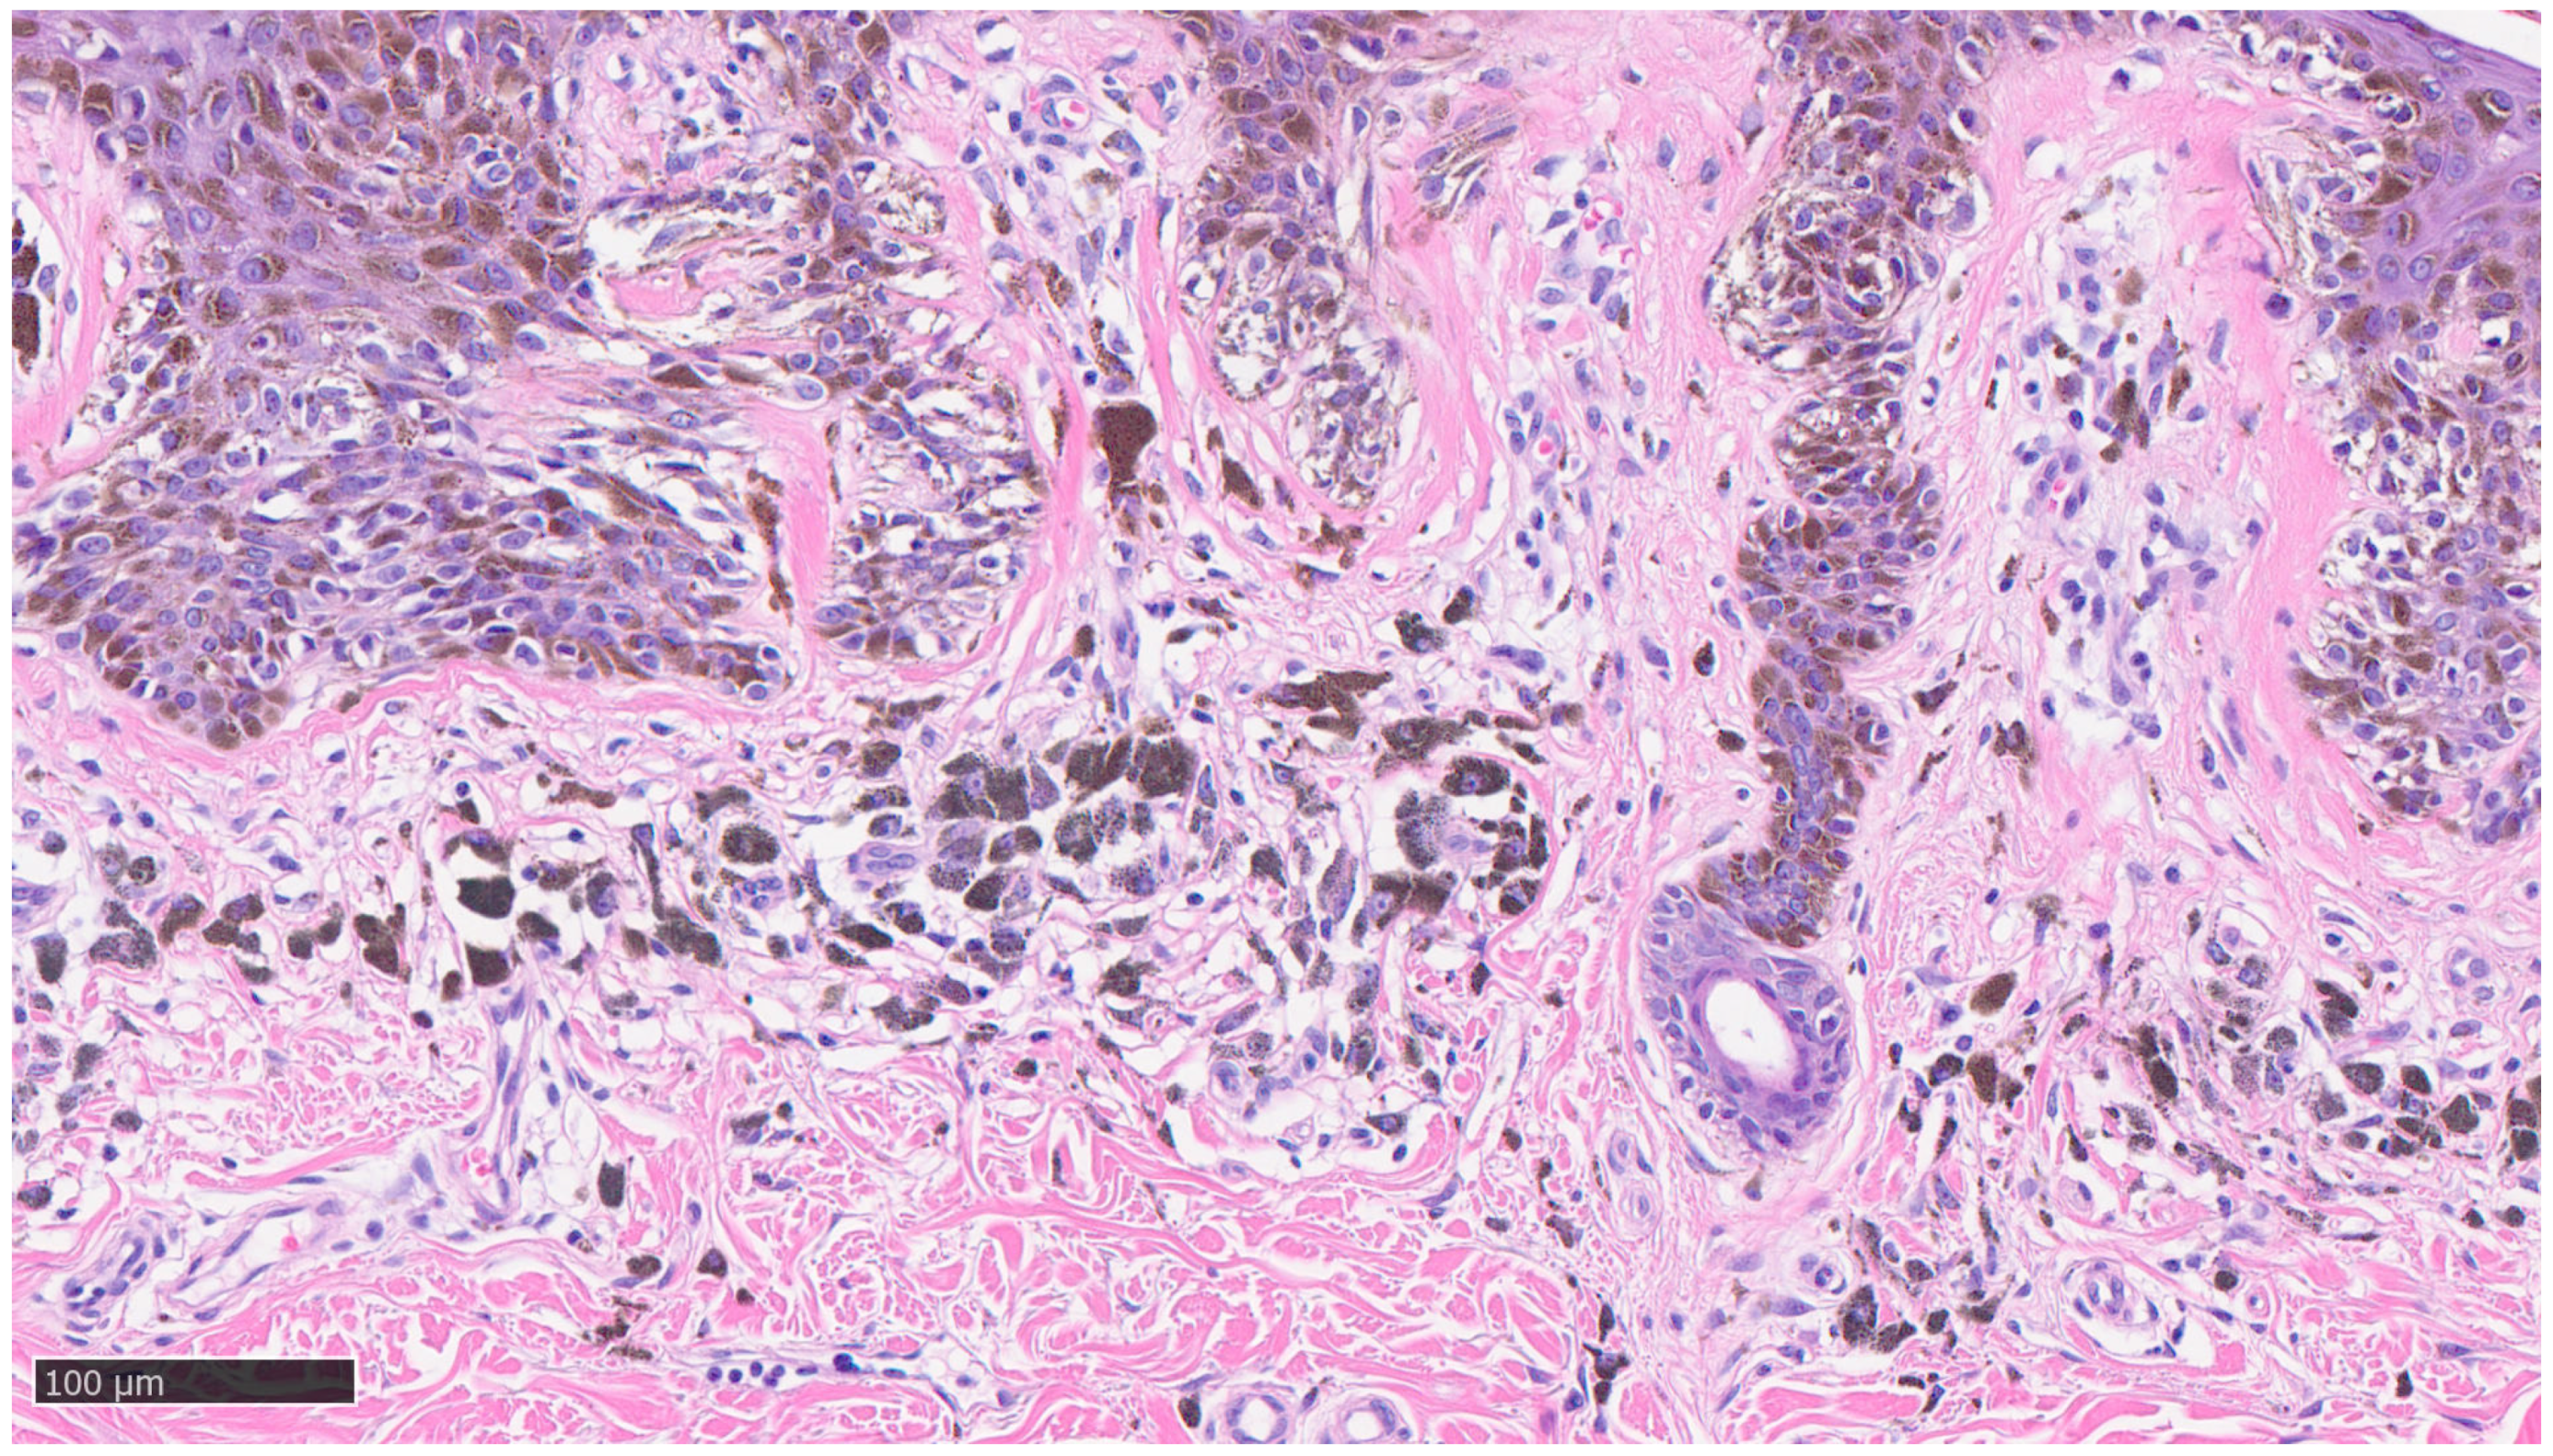

3.1. Histological Features of MIS and Regression